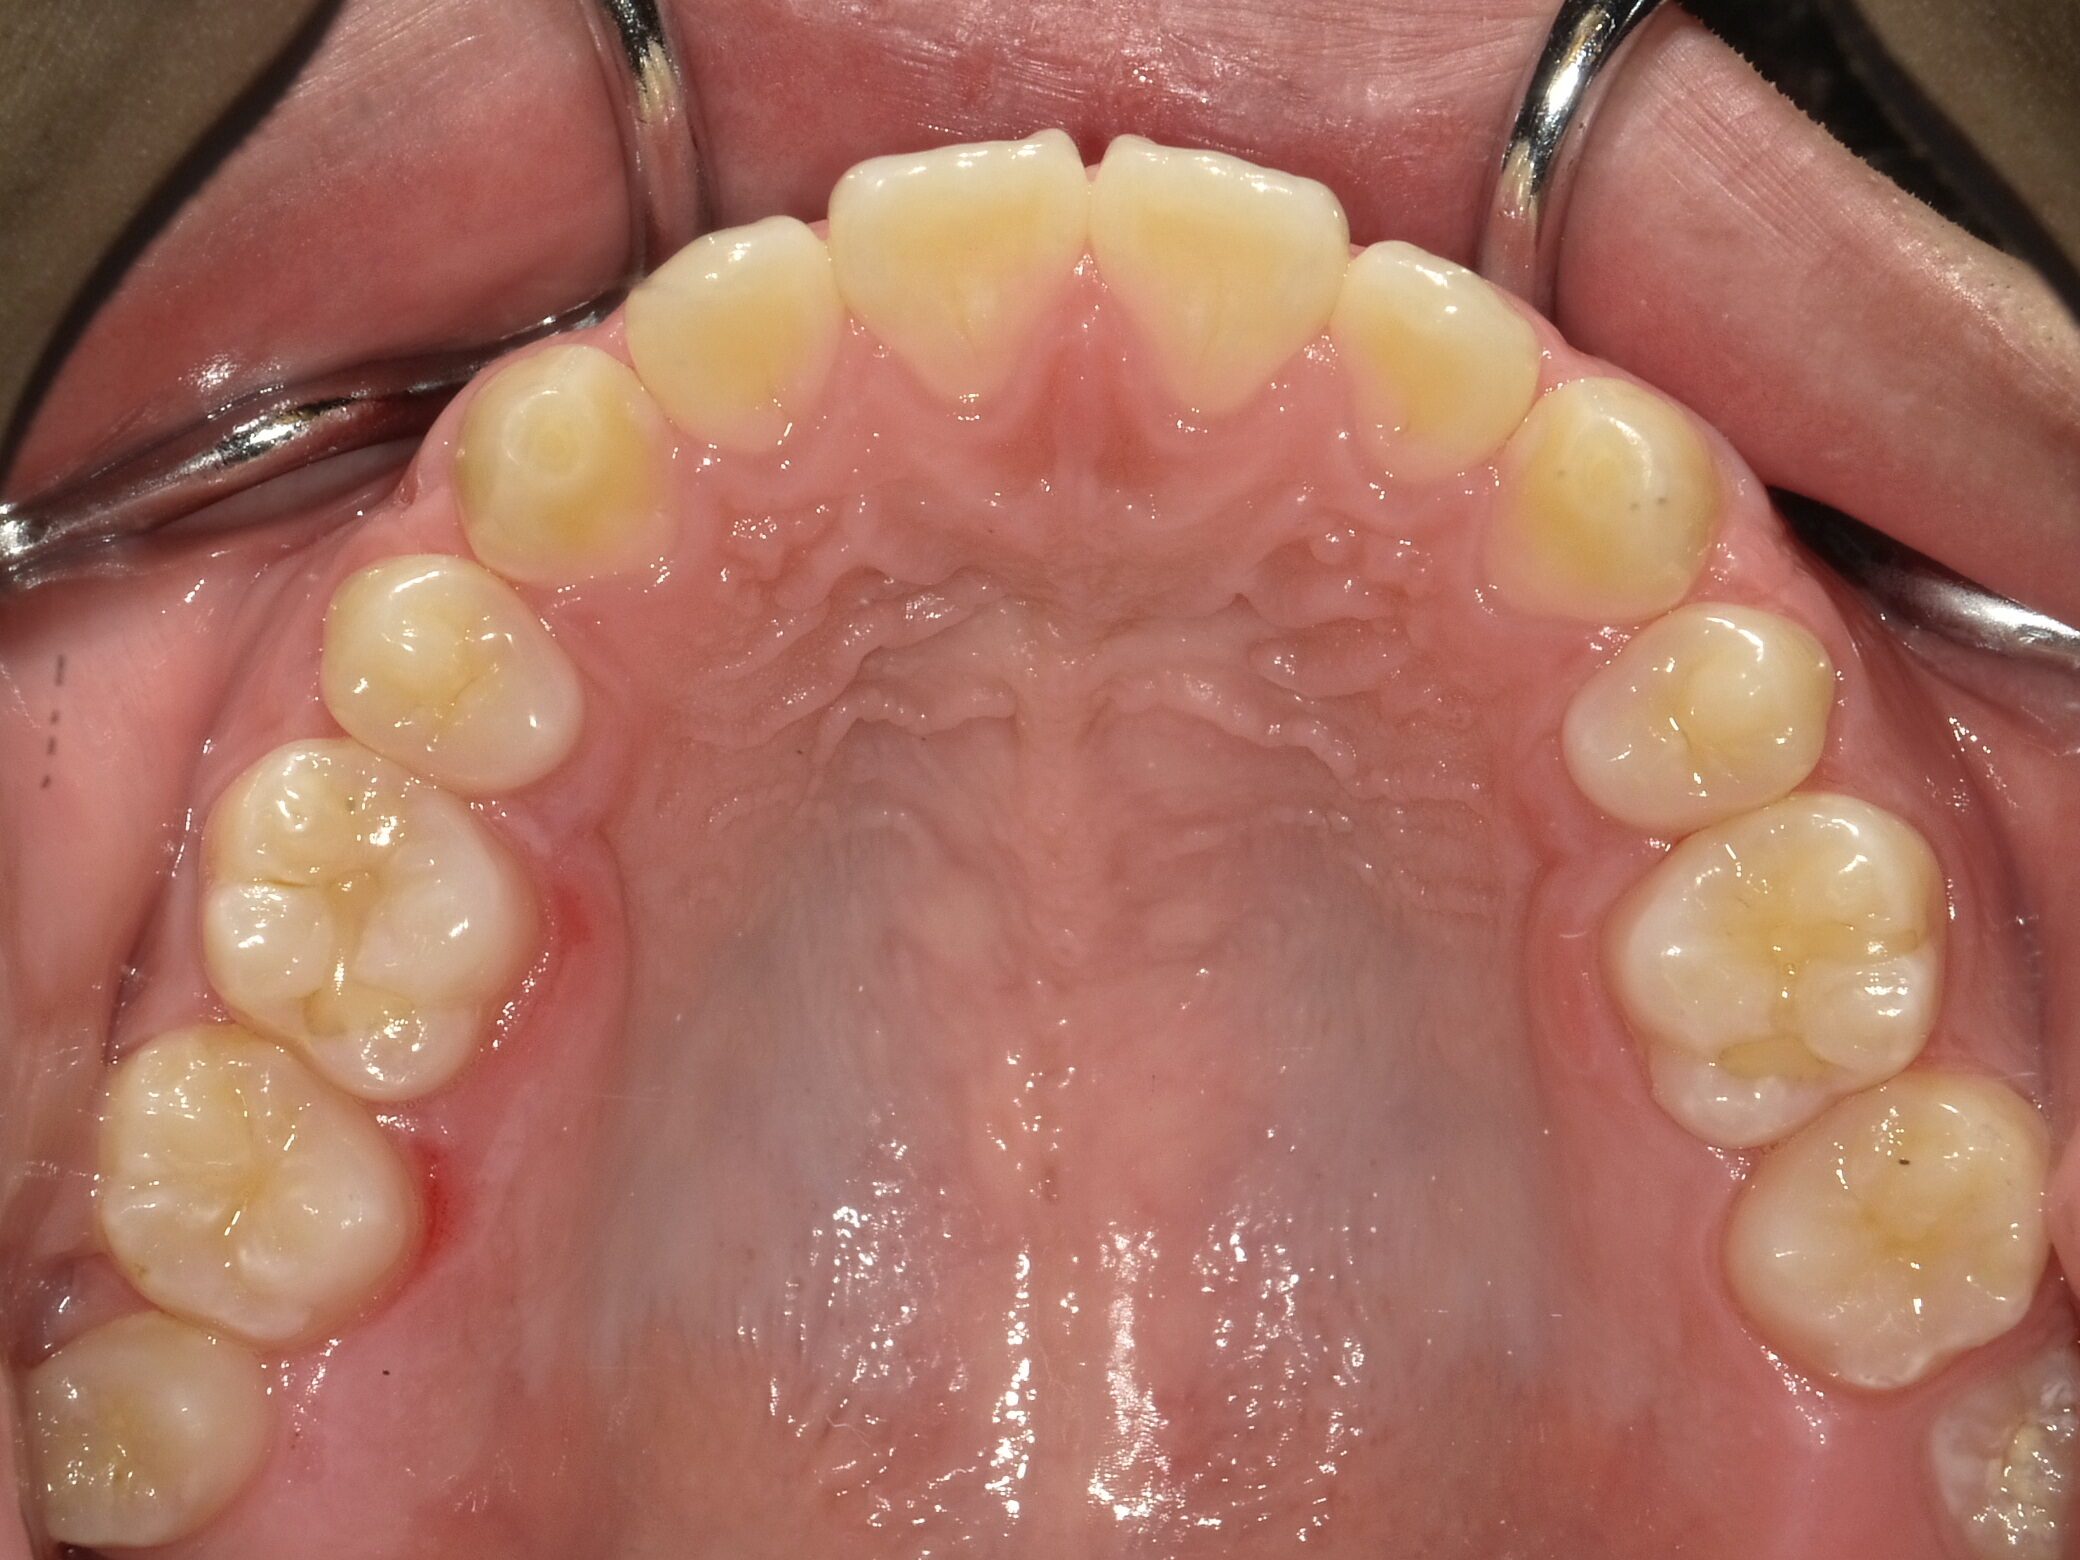

| 症例分類 | 上下顎前突 |

|---|---|

| 主訴 | 前歯が出ていて、口が閉じにくい |

| 年齢 | 20歳0ヶ月 |

| 性別 | 男性 |

| 抜歯部位 | 上下顎両側第一小臼歯 |

| 使用装置 | 歯の表側からのマルチブラケットによる矯正装置 |

| 治療期間 | 2年10ヶ月 |

| 保定装置 | 取り外し式保定装置 |

| 費用 | 相談料0円、検査料55,000円 動的矯正治療費935,000円 調整料6,600円×28回分 保定装置料0円 |

| リスク・注意点 | 上下の個々の歯の大きさに対して上下の顎が小さく歯が並ぶスペースが不足したために上下の前歯が前方に傾斜して、上下顎前突が生じています。これらを改善するために、上下顎両側第一小臼歯を抜歯して、このスペースを用いて歯を排列しました。歯の動き方には個人差があり、予想された治療期間が延長する可能性があります。 治療中は矯正歯科装置が歯の表面に付いており、歯が磨きにくくなるため、むし歯や歯周病が生じるリスクが高まります。ハミガキを適切に行ってお口の中を常に清潔に保ち、さらに、かかりつけ歯科医に定期的に受診することが大切です。 顎間ゴムの使用状況、定期的な通院など、矯正歯科治療には患者さんの協力が必要であり、それらが治療結果や治療期間に影響します。 治療の経過によっては当初予定していた治療計画を変更する可能性があります。 歯を動かすことにより歯根が吸収することがあります。 保定装置の装着時間が十分確保できない場合、歯並びや、咬み合せの「後戻り」が生じる可能性があります。 |